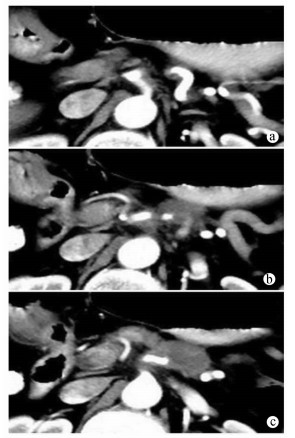

Hepatic Artery; Mesenteric Artery, Superior; Pancreatic Neoplasms

Allamyradov Aly, Yan DU, Tongtai LIU, Xiaodong WANG, Kai YAO

2021, 37(1): 163-164. DOI: 10.3969/j.issn.1001-5256.2021.01.034

Abstract(854) HTML (272) PDF (2322KB)(44)

Abstract: